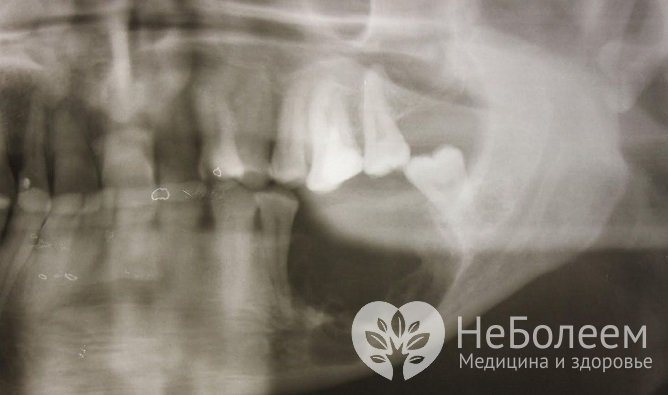

Диагностика основана на рентгенологических снимках (УЗИ не имеет ценности, КТ/МРТ только в ходе дифференциальной диагностики в непонятных случаях).